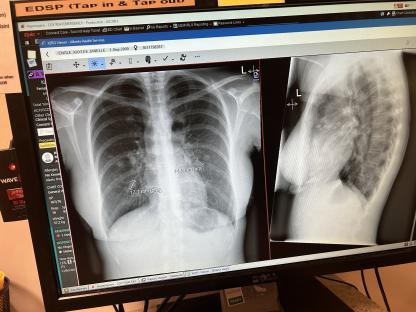

But a chest X-ray found the true cause â stage four melanoma, which had spread throughout her body, including seven tumours in her brain, and more than 20 tumours in each of her lungs.

“There were at least 20 tumours in each of my lungs â doctors were unable to count them all.

“They found seven brain tumours, at least 18 in my liver, and at least 20 in each lung, plus two beside my heart, and tumours in my spine and adrenal gland.